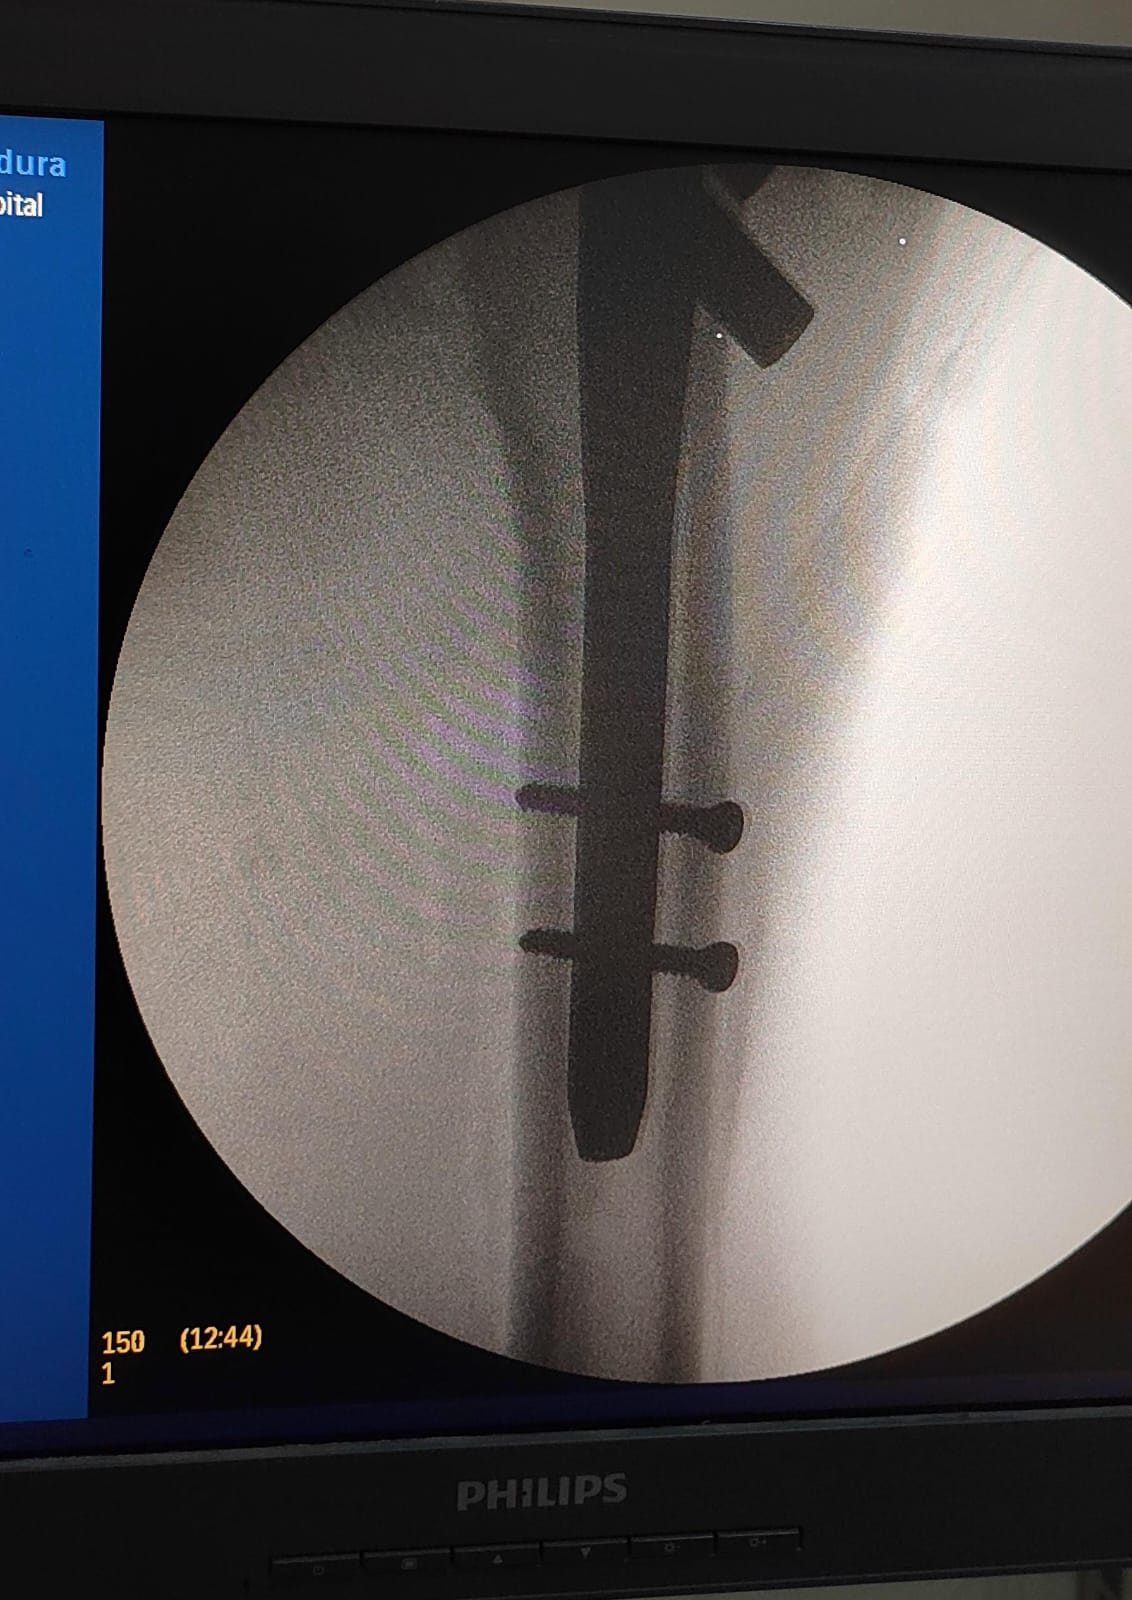

تركيب مسمار نخاعي بالفخذ الأيسر لمريض آخر.

وقد تمت العمليتان بدقة عالية وباستخدام أحدث التقنيات، وشارك فيهما فريق طبي وتمريضي وفني متكامل ضم:

الأطباء: د. شريف البيومي توفيق (عظام)، د. عيد السيد حسن (عظام)، د. ماهر فوزي كامل (تخدير).